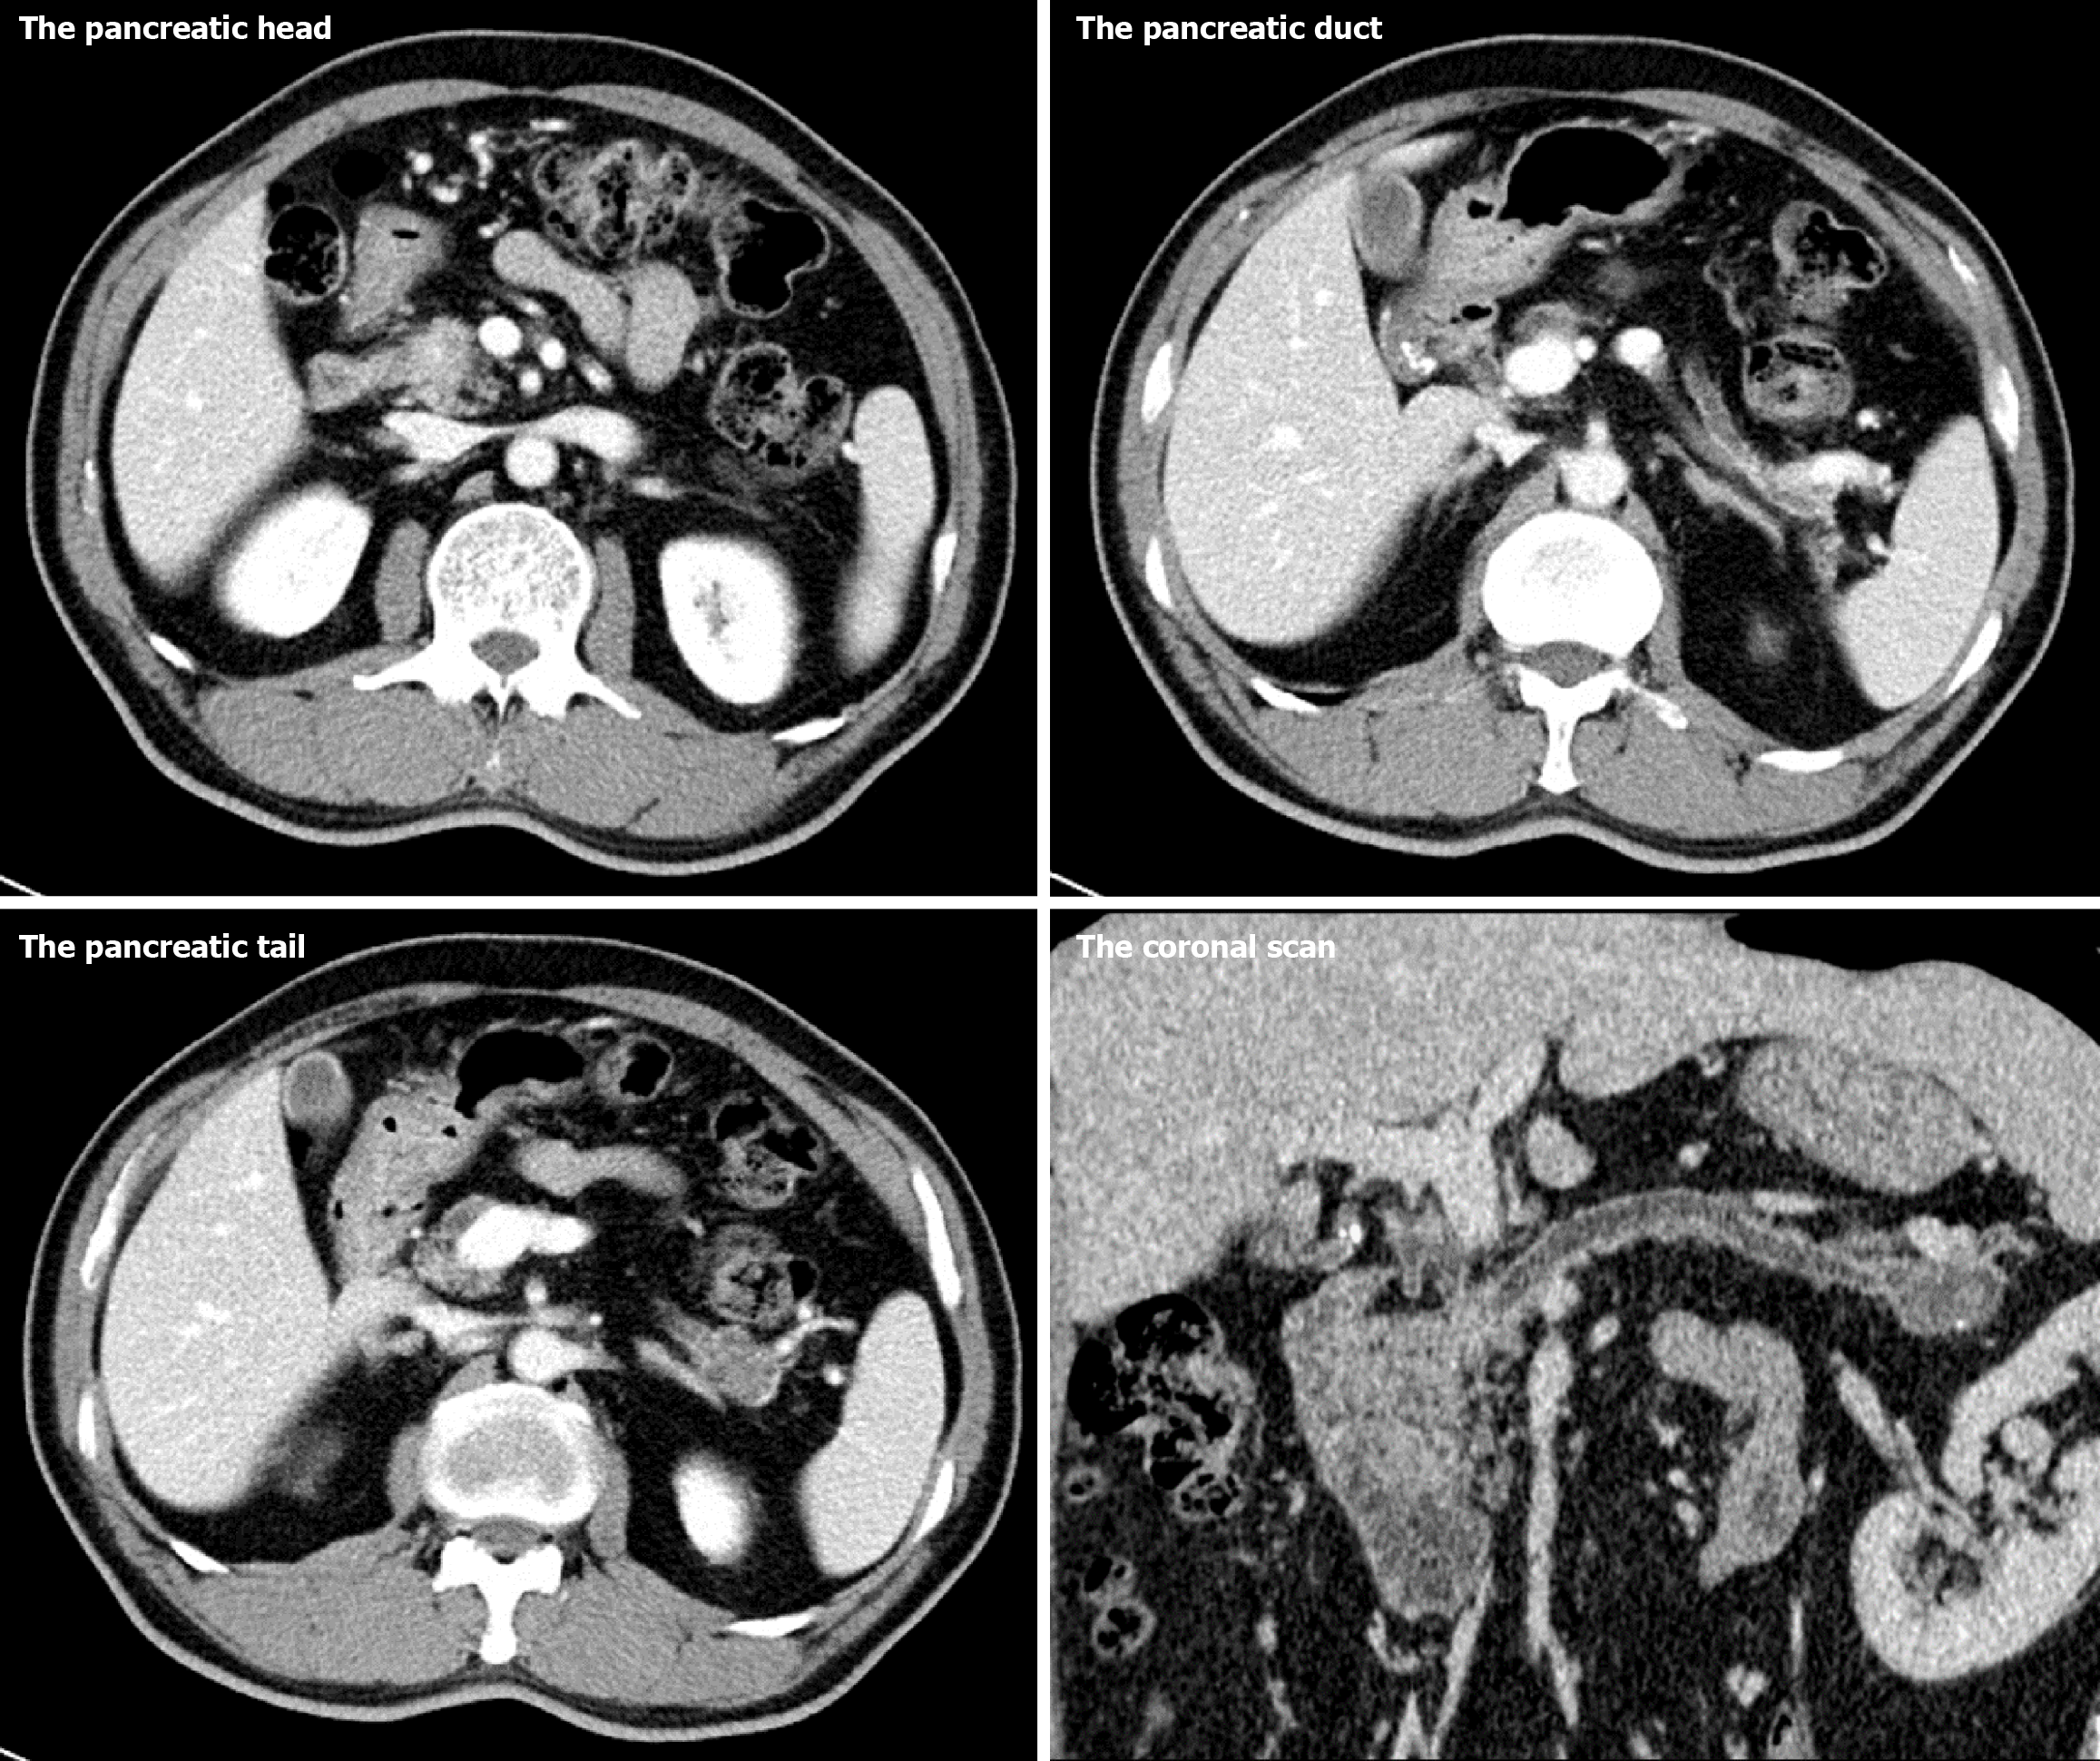

Figure 1 High-resolution computed tomography with three-dimensional reconstruction of the patient.